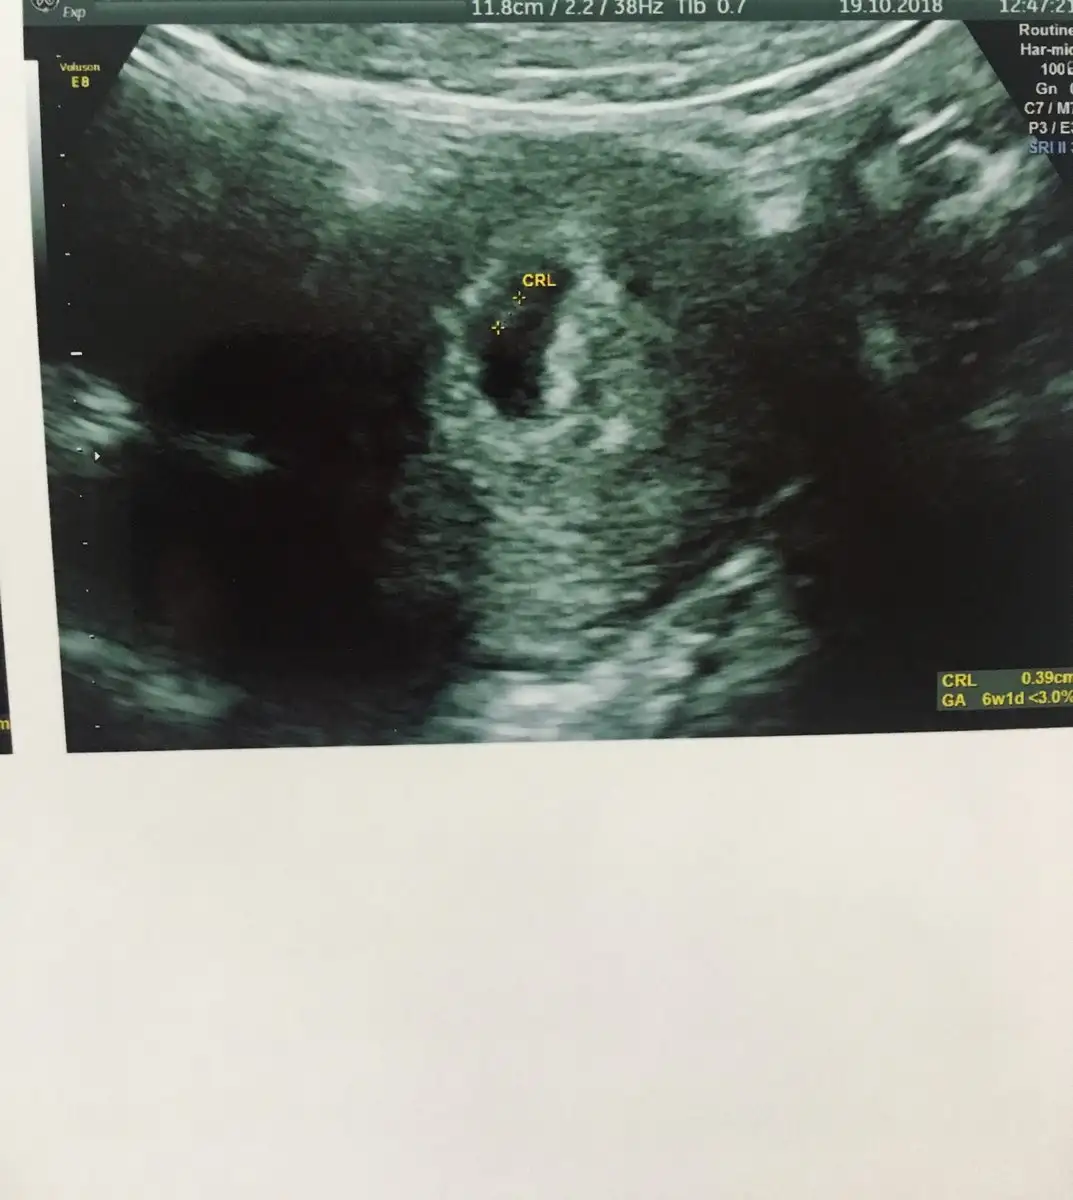

Paylaşırım tabi canım 9 haftalıktı bu görüntüde :)Usg görüntün varsa ilk haftaların paylaşır mısın bizimle

Heh bundan bahsedıyorum kızım sagdaydı senın solda :)))Paylaşırım tabi canım 9 haftalıktı bu görüntüde :)